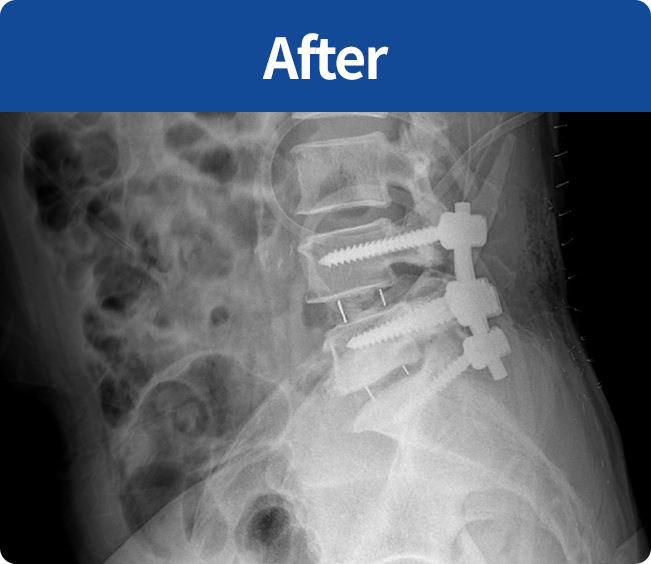

척추유합술

미세현미경을 통해 손상된 뼈와 인대조직을 제거하고 디스크의 역할을 해줄 인조 케이지를 삽입해

불안정한 척추체를 나사못으로 고정하는 수술 (척추 전방 골유합술, 척추 후방골유합술)